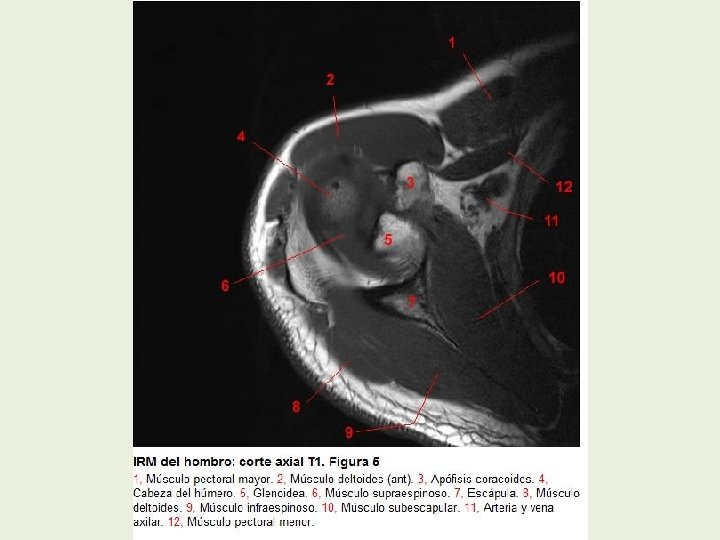

Hombro Cortes axiales RMN